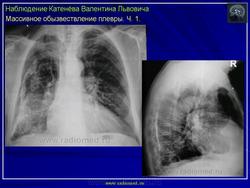

Обызвествления плевры